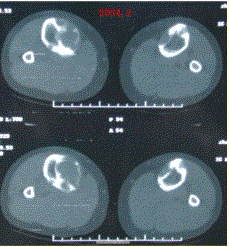

问题 患者女,20岁,右小腿疼痛1周。行双小腿正侧位CR,并行双小腿CT及MR扫描,见下图。 此病变最可能的诊断是

选项 A.骨囊肿 B.动脉瘤样骨囊肿 C.骨纤维异常增生症 D.骨巨细胞瘤 E.非骨化性纤维瘤

答案 C